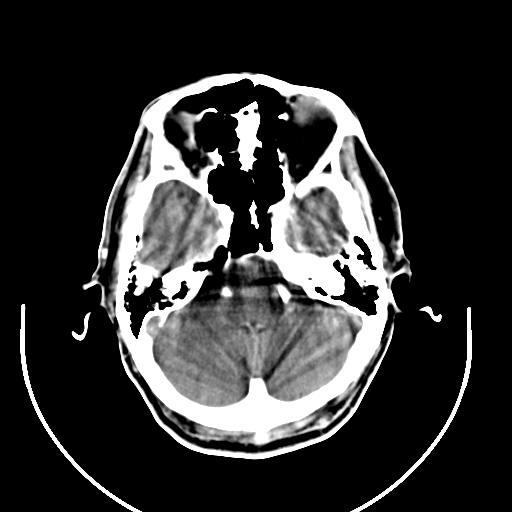

以下是引用拾荒者在2008-7-26 15:36:00的发言:[br]侧脑室内高密度钙化影,未见软组织结构,侧脑室未见增大,考虑良性钙化性改变(钙化型脑膜瘤可能)。

以下是引用宇宙ct在2008-7-26 13:43:00的发言:[br]支持:钙化性脑膜瘤。 不排除脉络膜瘤 [br] [br]